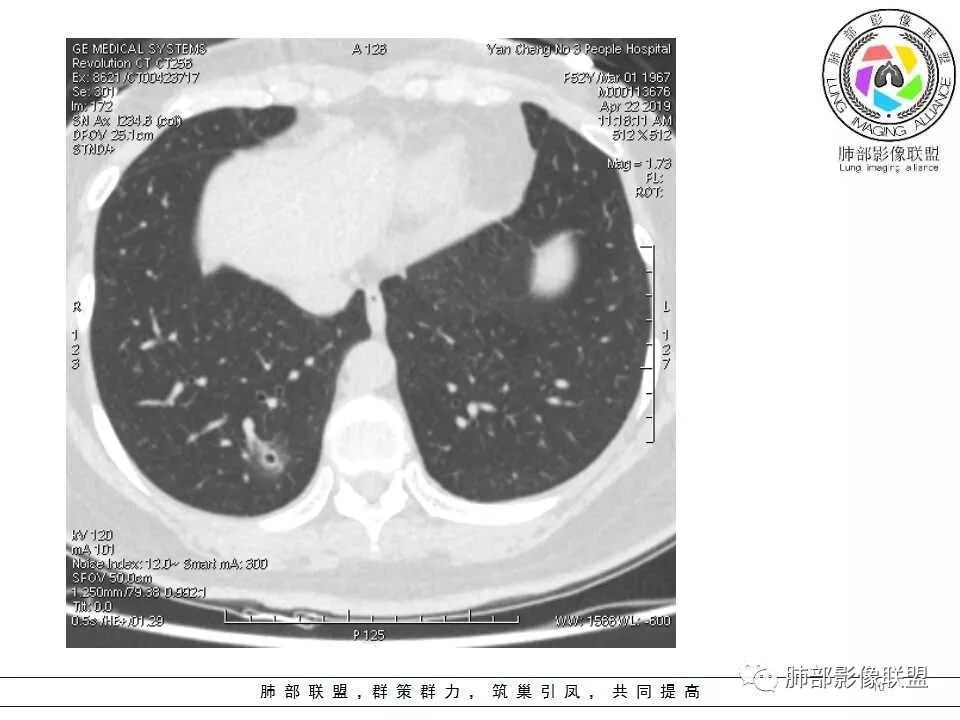

体检发现肺部结节,右下肺混合密度结节,结节中心空泡,壁光滑,结节边缘模糊,血管在结节内增粗,矢状位前基底段还有一片磨玻璃影,所以考虑良性结节可能,炎性肉芽肿?抗炎后复查。腺癌合并炎性改变待排。

晨读:中老年女性,体检来诊。右肺下叶后基底段近胸膜下mGGN,其内实性成分似见毛刺及分叶,并见空泡征,周围GGO边界清楚,近肺门端见血管影伸入病灶并略显扩张,病变与支气管关系观察欠佳。多考虑恶性,腺癌可能性大。鉴于首次检查,常规建议抗炎治疗后复查,观察病灶变化情况,再决定下一步诊疗方向。

大家考虑恶性的依据?炎性的依据?首先这是不是磨玻璃结节?依据是啥?

因为密度比肺组织高,但是又遮盖不了血管,所以GGO明确

是pGGO?mGGO?

实性的部分超过10%——mGGO

GGO边缘清不清?依据?

部分清,部分不清

依据:能不能沿GGO边缘画出一个边界

能否勾勒出边界?是否有血管?

排除血管的边缘,边界清吗?

可惜的是背景也模糊了一些